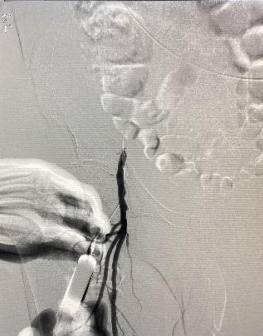

遂果断另辟蹊径,经肱动脉穿刺成功,行腹主动脉造影证实右侧髂总动脉闭塞,左侧髂总动脉极重度狭窄并串珠样改变,故经股动脉入路此路不通。

头颈部血管造影提示:患者为右侧颈内动脉极重度狭窄合并右侧大脑中动脉闭塞。